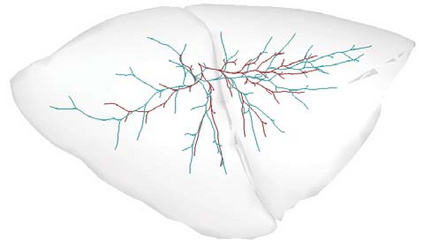

Recent advances in imaging techniques have enabled us to visualize lung tumors or nodules in early-stage cancer. However, the positions of nodules can change because of intraoperative lung deflation, and the modeling of pneumothorax-associated deformation remains a challenging issue for intraoperative tumor localization. In this study, we introduce spatial and geometric analysis methods for inflated/deflated lungs and discuss heterogeneity in pneumothorax-associated deformation. Contrast-enhanced CT images simulating intraoperative conditions were acquired from live Beagle dogs. Deformable mesh registration techniques were designed to map the surface and subsurface tissues of lung lobes. The developed framework addressed local mismatches of bronchial tree structures and achieved stable registration with a Hausdorff distance of less than 1 mm and a target registration error of less than 5 mm. Our results show that the strain of lung parenchyma was 35% higher than that of bronchi, and that subsurface deformation in the deflated lung is heterogeneous.